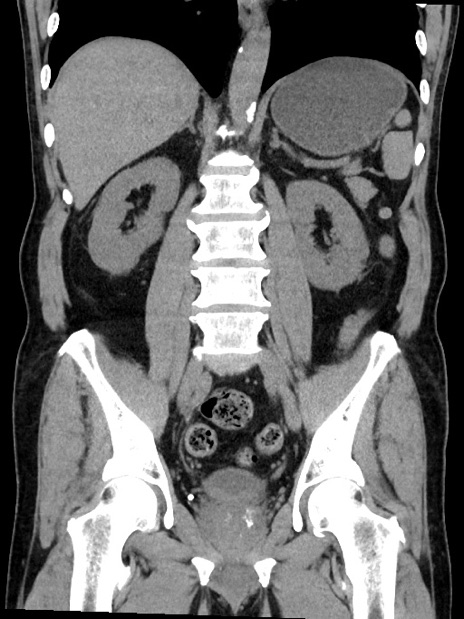

症例35(冠状断像)

【症例】70歳代 男性

【主訴】腹部膨満、嘔吐

【現病歴】昨日より腹部膨満感出現。本日増悪し、仙痛出現。嘔吐あり、受診。

【既往歴】糖尿病、胆摘後

【身体所見】BP 149/80mmHg、HR 74/min、BT 35.9℃、腹部:膨満、軟、圧痛なし。腸雑音減弱あり。上腹部正中切開瘢痕あり。

【データ】WBC 13500、CRP 1.72